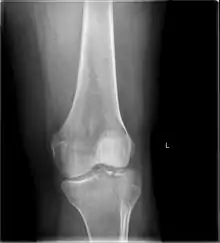

In all injuries to the tibial plateau radiographs (commonly called x-rays) are imperative. Computed tomography scans are not always necessary but are sometimes critical for evaluating degree of fracture and determining a treatment plan that would not be possible with plain radiographs.[5] Magnetic Resonance images are the diagnostic modality of choice when meniscal, ligamentous and soft tissue injuries are suspected.[6][7] CT angiography should be considered if there is alteration of the distal pulses or concern about arterial injury.

Subtle tibial plateau fracture on an AP X ray of the knee Subtle tibial plateau fracture on an AP X ray of the knee

A tibial plateau fracture seen on X-ray A tibial plateau fracture seen on X-ray